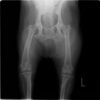

左後肢の挙上を主訴に来院されました。触診にて両関節の前方引き出し兆候、両膝蓋骨の内方脱臼を認めました。関節液検査より免疫介在性多発性関節炎は否定的でした。レントゲン検査にてfat pad signを伴う関節炎が認められたことから、前十字靭帯断裂と膝蓋骨内方脱臼(左GradeⅢ 右GradeⅢ〜IV)併発と診断し、手術を行いました。

術前正面像

術前のTPAは左後肢33.1°右後肢26.8°でしたがTPLO実施により左後肢5.5°右後肢12°に矯正されました。